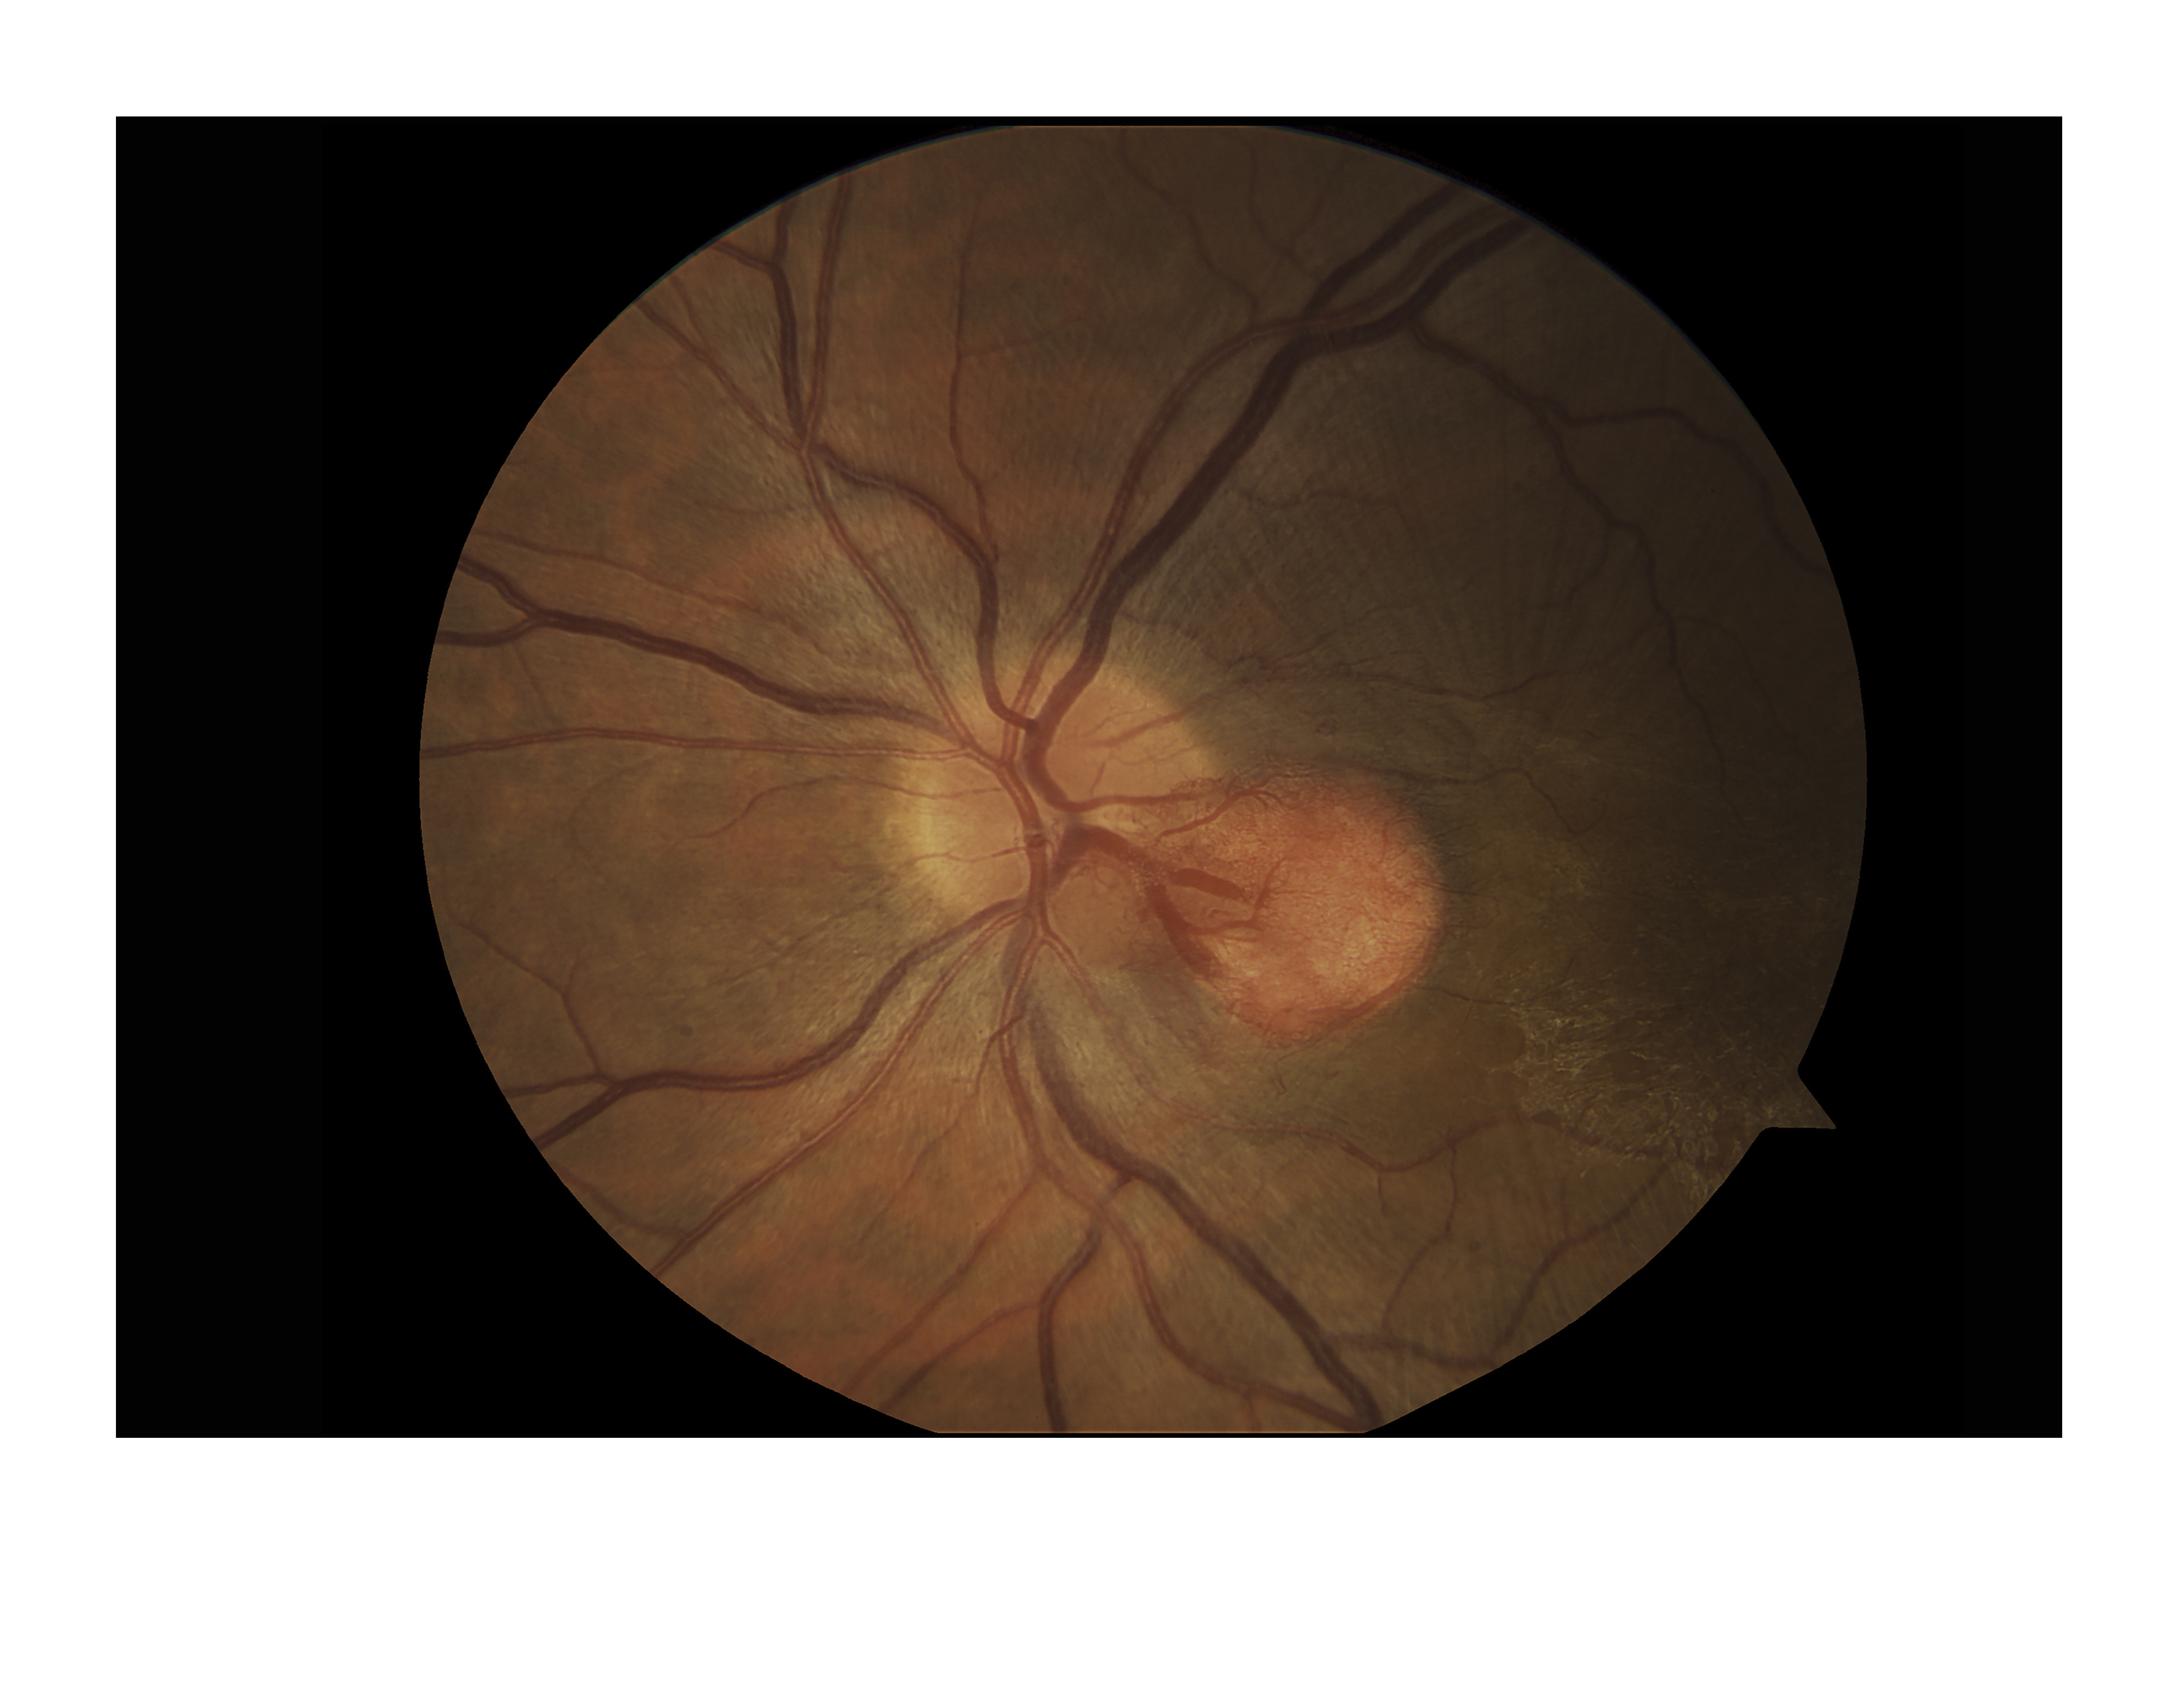

Hemangioblastoma

Presented by Judith Gulian, OCT-C

This photograph received Honorable Mention in the category "Fundus Photography - Normal 30-40" and was displayed in the 2024 OPS Exhibit.